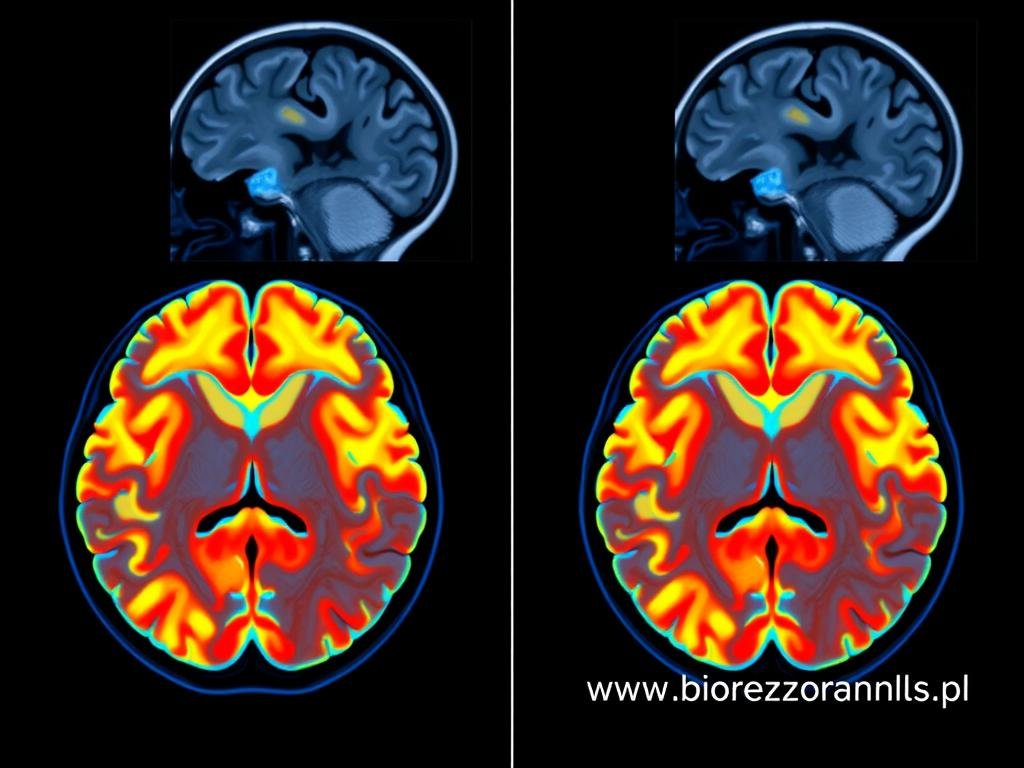

Technologia Biorezonans NLS (Non-Linear System) opiera się na analizie subtelnych sygnałów elektromagnetycznych generowanych przez tkanki i komórki organizmu. W kontekście diagnostyki neurologicznej, urządzenie rejestruje i analizuje wzorce częstotliwości charakterystyczne dla zdrowych i zmienionych chorobowo struktur układu nerwowego.

Każda komórka nerwowa emituje specyficzne fale elektromagnetyczne o określonej częstotliwości. W przypadku zaburzeń funkcjonowania, częstotliwości te ulegają zmianie. Urządzenie Biorezonans NLS wykrywa te subtelne różnice, umożliwiając identyfikację potencjalnych problemów neurologicznych, zanim staną się one widoczne w konwencjonalnych badaniach obrazowych.

Technologia Biorezonans NLS znajduje zastosowanie w diagnostyce szerokiego spektrum chorób i zaburzeń neurologicznych. Dzięki zdolności do wykrywania subtelnych zmian na poziomie komórkowym, może stanowić cenne uzupełnienie konwencjonalnych metod diagnostycznych.

Stwardnienie rozsiane (SM) to przewlekła choroba autoimmunologiczna, w której układ odpornościowy atakuje osłonki mielinowe neuronów. Wczesna diagnostyka ma kluczowe znaczenie dla skutecznego leczenia. Biorezonans NLS umożliwia wykrycie subtelnych zmian w strukturze mieliny, zanim staną się one widoczne w badaniach MRI.

Diagnostyka neurologiczna dysponuje szeregiem metod badawczych, od badania klinicznego po zaawansowane techniki obrazowania. Biorezonans NLS nie zastępuje tych metod, ale stanowi cenne ich uzupełnienie, oferując unikalne możliwości diagnostyczne.

| MRI (rezonans magnetyczny) | Obrazowanie struktury tkanek za pomocą pola magnetycznego | Wysoka rozdzielczość obrazu, dobra wizualizacja tkanek miękkich | Wysoki koszt, długi czas badania, przeciwwskazania (implanty metalowe) | Biorezonans NLS może wykryć zmiany funkcjonalne przed pojawieniem się zmian strukturalnych widocznych w MRI |

| PET (pozytonowa tomografia emisyjna) | Obrazowanie metabolizmu tkanek | Ocena funkcjonalna, wykrywanie zmian metabolicznych | Wysoki koszt, ograniczona dostępność, ekspozycja na promieniowanie | Biorezonans NLS oferuje podobne informacje funkcjonalne bez narażenia na promieniowanie |